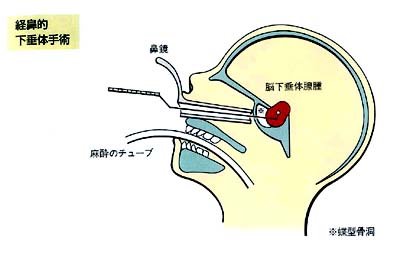

経鼻的下垂体手術(経蝶形骨下垂体手術)

正確には、経蝶形骨下垂体手術といいます。

まず、上の前歯の付け根の口腔粘膜を横に2cm程度切開し、鼻腔の裏側に相当する部分に入ります。鼻の粘膜を左右に圧排し、特殊な鼻鏡を挿入します。

ここで、手術用の顕微鏡をセットし、蝶型骨洞という副鼻腔(鼻の奥の骨に囲まれた空間)を開きます。その粘膜や隔壁を除くと、脳下垂体の直下に到達出来ます。そこで薄い骨の壁を開くと、脳下垂体(および腫瘍)が硬膜という比較的しっかりした膜に包まれてでてきます。

この硬膜を切開し、腫瘍を摘除します。この際正常の下垂体組織は腫瘍の周辺に圧排されて残存しており、これと区別しながら腫瘍を選択的に摘出することが可能です。

この手術の特徴

腫瘍を十分摘除したら、空虚となったスペースに筋肉片や脂肪片をパックします。これらは通常右の大腿部から採取します。その後、脳下垂体の底部を小さなセラミック片でふさぎ、手術用の接着剤で固定します。

鼻鏡を外して口腔粘膜を縫合し、鼻腔内を抗生物質付ガーゼで十分パックします。口の中を縫合した糸は抜糸せず、自然に脱落するのを待ちます。これには約1か月かかります。